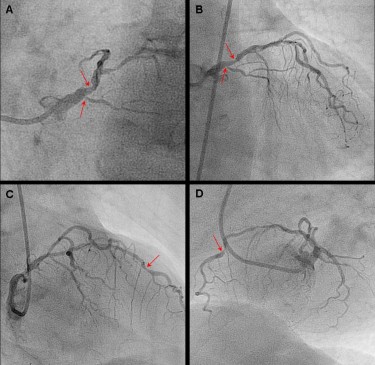

90 - 100 Schlägen pro Minute oder Tachykardien die auf Vorhofflimmern die Herzvorhöfe schlagen nicht mehr regelmäßig sondern vollführen zahlreiche Flimmerbewegungen oder Vorhofflattern. 52 männlich mit Angina pectoris eingeschlossen die wegen des Verdachts auf eine stenosie-rende KHK eine kardiale Adenosin-Stress-Perfusions-MRT inklusive Cine-Ruhe-Funktion Adenosin-Stress- und -Ruhe-Perfusion und Late gadolinium enhancement und. Kombiniert wird die Untersuchung mit einer myokardialen Vitalitätsdiagnostik Late-Enhancement zur Identifizierung infarzierter MyokardbezirkeFibroseEntzündung.

Https Www Klinikum Uni Heidelberg De Fileadmin Radiologie Radiodiagnostik Lehre Fortbildung Korosoglou Was Kann Mrt Mehr Pdf